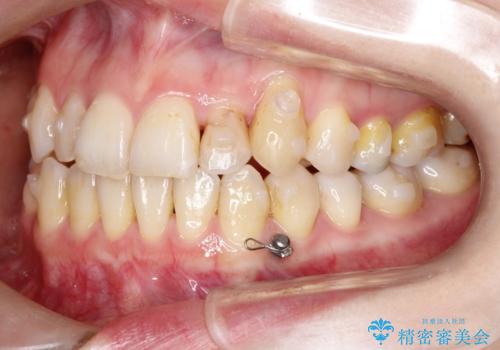

抜歯は行わず上顎の奥のスペースを利用して歯をスライドする方法の他に歯列弓の拡大やディスキング(歯と歯の間の隙間を作る処置)を行い叢生を改善しましています。

歯の大きさの不揃いが原因の正中のズレは、ディスキング量を調整することで合わせました。

矯正装置としてはマウスピースを使用しています。